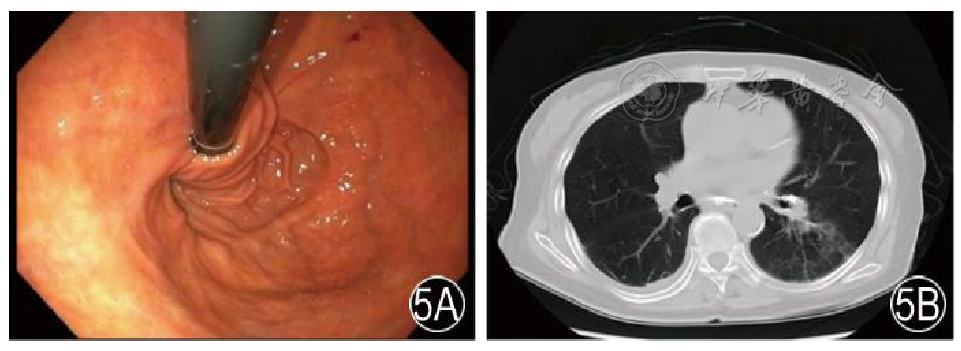

图5 术后胃镜及出院前CT检查 5A 术后胃镜检查(第21天),显示食管裂孔关闭,胃底包绕食管良好,未见瘘口;5B 出院前CT检查示瘘口闭合,胸腔积液吸收,肺部炎症明显减轻